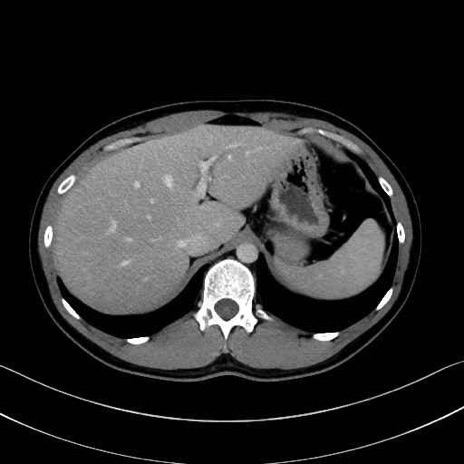

腰方形筋(quadratus lumborum muscle)のCT画像の解剖

1. 体幹部(腹部・背部・後腹壁)の筋肉

腹直筋 (Rectus abdominis)

外腹斜筋 (External oblique)

内腹斜筋 (Internal oblique)

腹横筋 (Transversus abdominis)

腰方形筋 (Quadratus lumborum)

広背筋 (Latissimus dorsi)

脊柱起立筋 (Erector spinae)

多裂筋 (Multifidus)